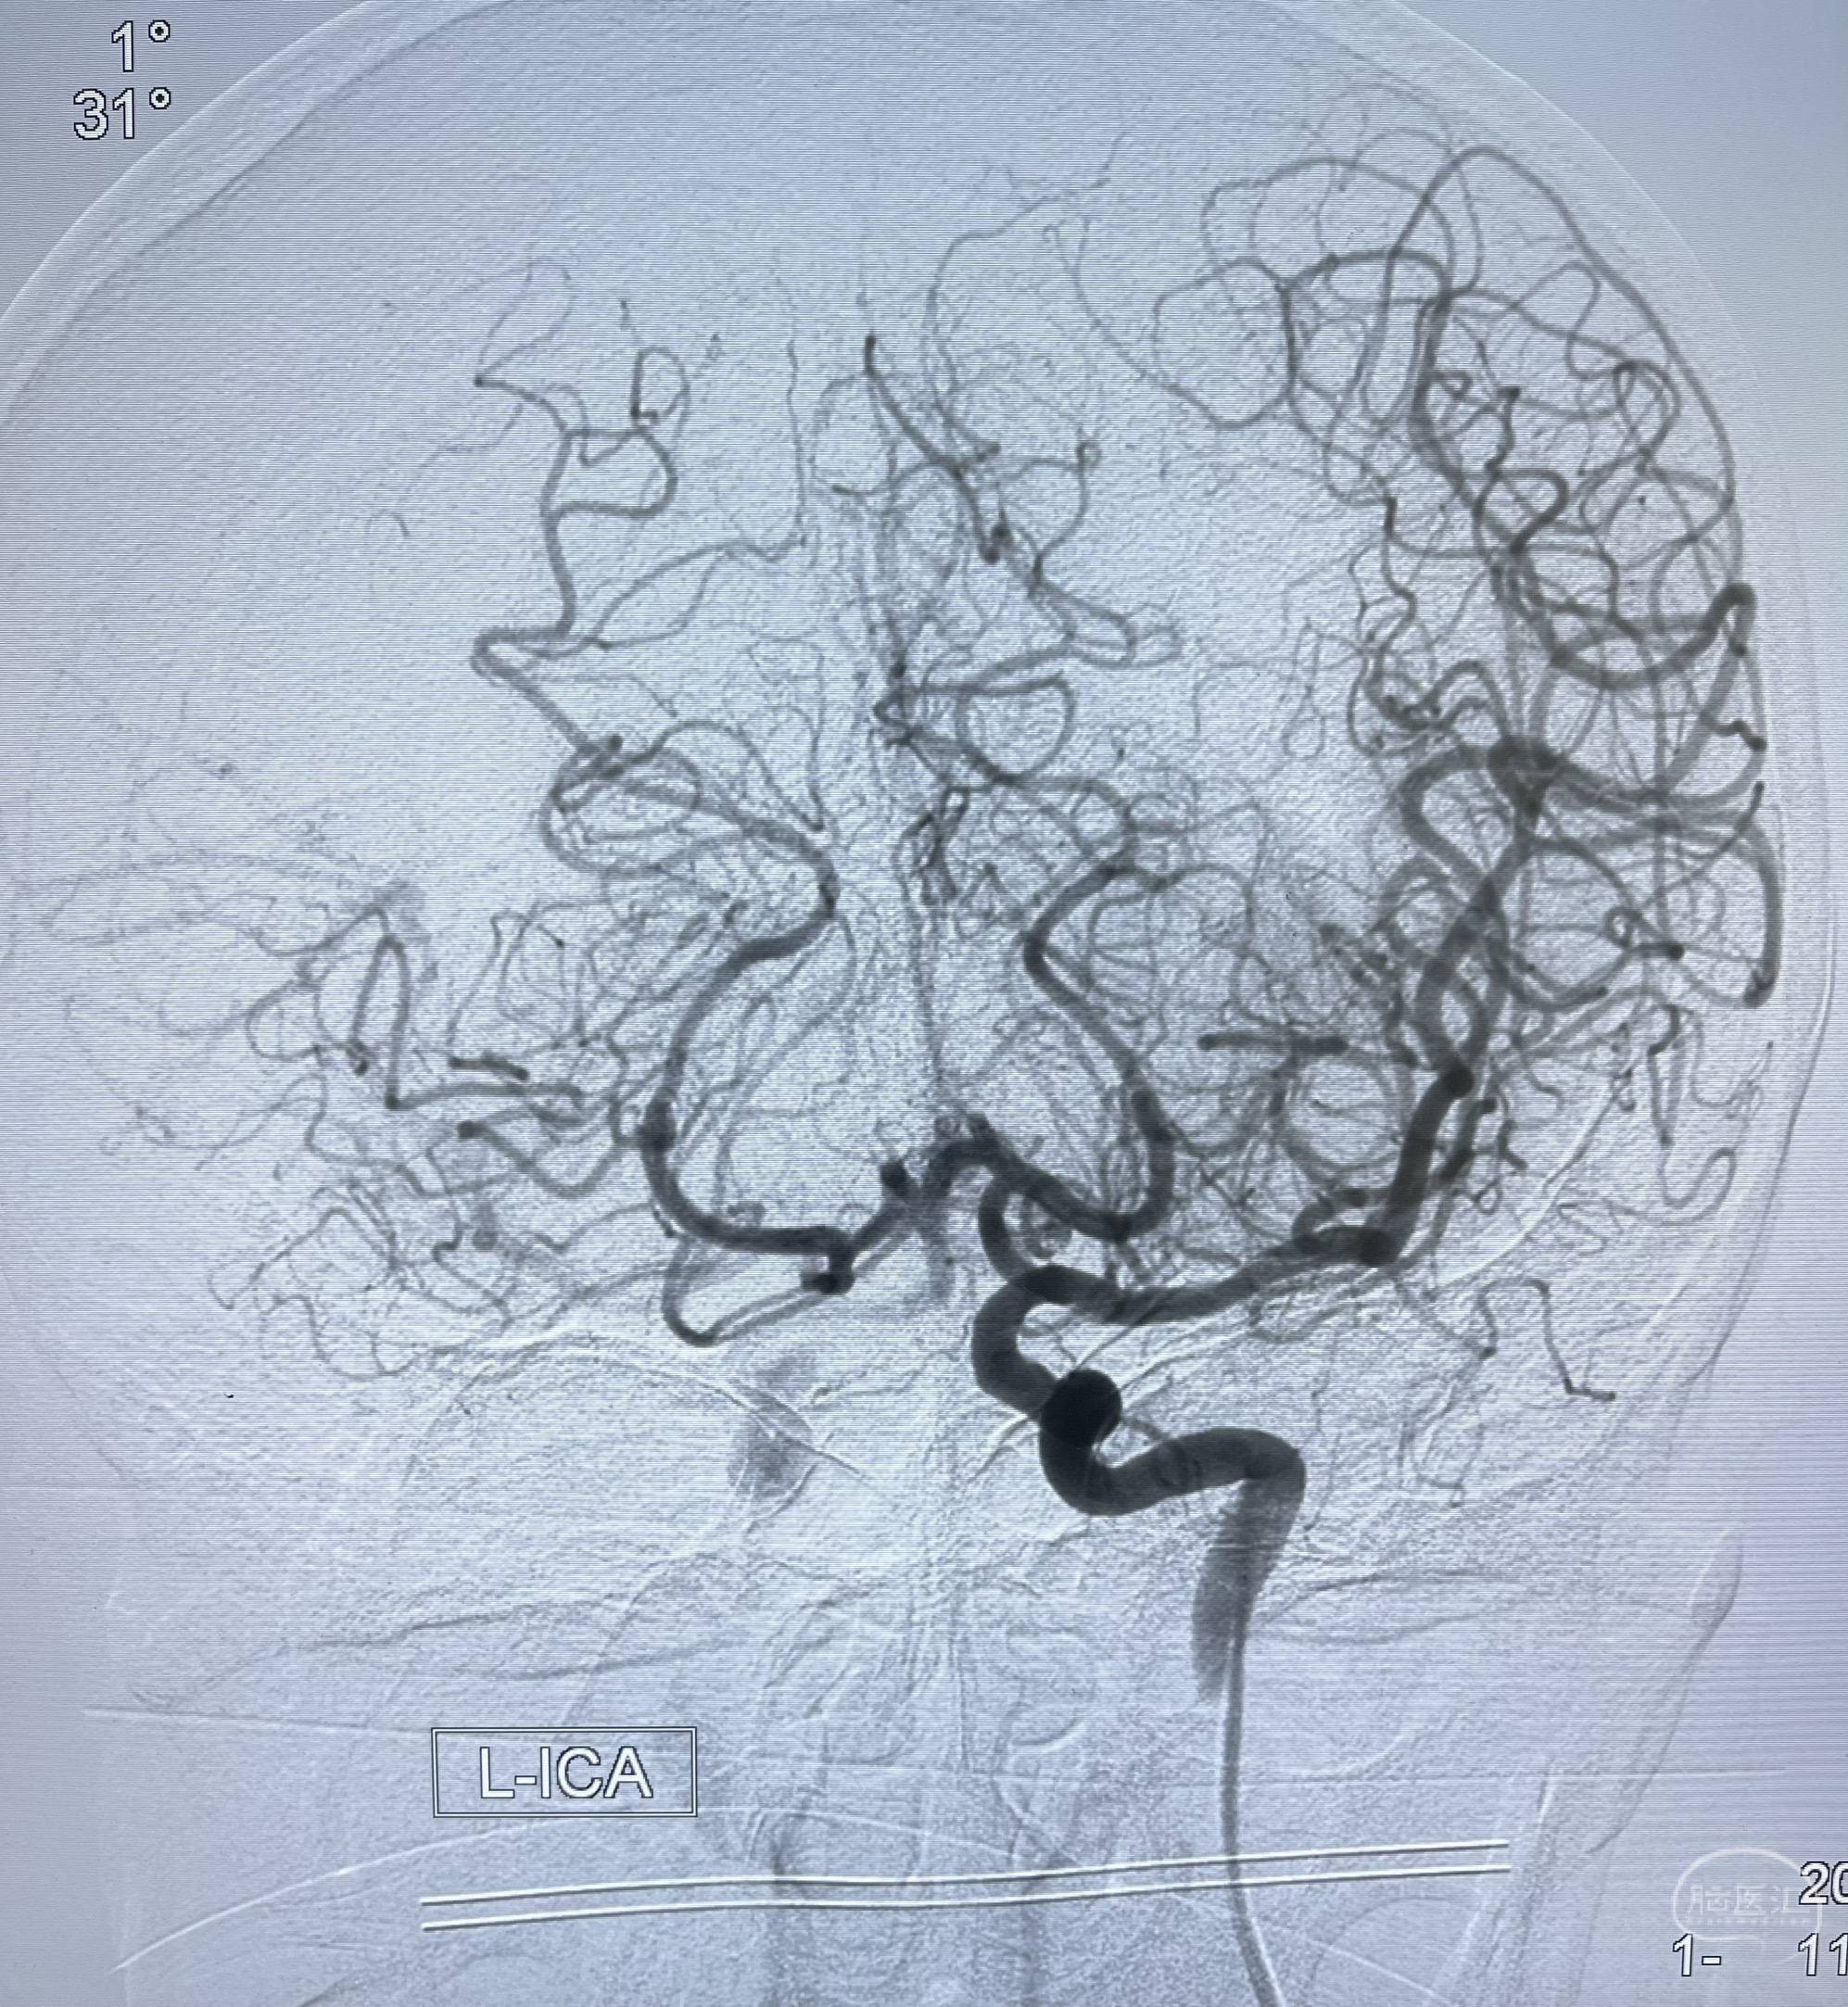

脑血管造影2023.03.06:右侧颈内动脉颈段至岩骨段闭塞,可见后后循环通过原始三叉动脉吻合代偿至海绵窦段,后交通区可见囊状造影剂填充影,左侧锁骨下动脉呈“残端”改变,呈“右侧颈总动脉支架成形术后改变”,支架内血流通畅,可见后交通吻合显影至左侧大脑后动脉,并可见左枕动脉吻合椎动脉至锁骨下动脉

2023-03-06DSA:

1.右侧颈内动脉及左侧锁骨下动脉闭塞

2.右侧颈内动脉由后循环经右侧后交通动脉前向代偿显示

3.右侧颈内动脉眼动脉段近后交通动脉处重度狭窄伴前壁不规则动脉瘤

4.右侧颈外动脉可见经由右侧脑膜中动脉吻合显影右侧眼动脉及颈内动脉

5.左侧颈总动脉起始部支架术后

6.左侧颈外动脉可见吻合显影至左侧椎动脉并逆行供血至左侧腋动脉

7.左侧锁骨下动脉闭塞

1.箭头处为右侧颈内动脉后交通动脉处重度狭窄,狭窄前壁为不规则动脉瘤;

2.狭窄远端颈内动脉由左侧颈内动脉经左侧后交通动脉—基底动脉顶—右侧后交通—右侧颈内动脉—右侧大脑中动脉途径代偿

左侧颈内动脉经左侧后交通动脉—基底动脉顶—右侧后交通—右侧颈内动脉—右侧大脑中动脉途径代偿